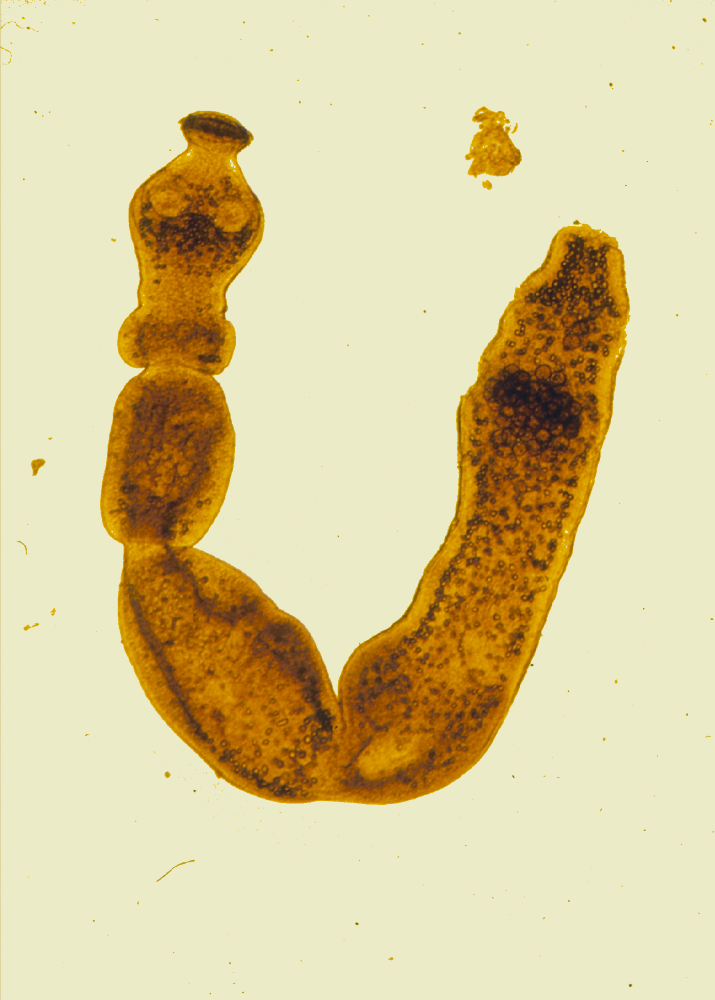

Fuchsbandwurm: Wiederentdeckung eines verschollen geglaubten Parasiten11. Juni 2025 Im Jahr 1863 beschrieben, jetzt wiederentdeckt: Das Typusexemplar des Fuchsbandwurms (Echinococcus multilocularis). Foto: © Senckenberg Der Fuchsbandwurm gilt seit Jahrzehnten als gut beschrieben und bekannt. Dennoch fehlte bislang eine genetisch abgesicherte Referenz des humanmedizinisch relevanten Parasiten, da das ursprüngliche Typusmaterial als verschollen galt. Überraschend wurde dieses historische Material in den Senckenberg Naturhistorischen Sammlungen Dresden wiederentdeckt. In einer neu veröffentlichten Studie ordnen die Forschenden mit moderner Genomsequenzierung den Fuchsbandwurm ein und klären seine Verwandtschaft mit anderen Bandwurmarten. Die Wiederentdeckung veranschaulicht, welche wichtige Rolle wissenschaftliche Sammlungen haben und wie diese eine Grundlage für verlässliche Diagnostik und Forschung schaffen. Der Fuchsbandwurm (Echinococcus multilocularis) ist ein nur wenige Millimeter langer Parasit mit großer Wirkung. Der vor allem im Darm von Füchsen lebende Bandwurm kann für den Menschen zur Bedrohung werden – etwa durch den Verzehr von Beeren oder ungewaschenem Gemüse, das mit Eiern des Parasiten verunreinigt ist. In diesem Fall kann sich in der Leber eine sogenannte „alveoläre Echinokokkose“ entwickeln, eine seltene, aber ernsthafte Erkrankung, die einem Tumor ähnelt und unbehandelt lebensbedrohlich sein kann.„Echinococcus multilocularis zählt in der nördlichen Hemisphäre zu den gefährlichsten Parasiten, die vom Tier auf den Menschen übertragen werden können. Entsprechend groß ist das Interesse an dem Tier, sowohl in der Forschung als auch in der Öffentlichkeit“, erläutert Dr. Thomas Romig, Parasitologe und Fuchsbandwurmexperte der Universität Hohenheim und fährt fort: „Seit über 70 Jahren gilt die Einordnung dieser Art – basierend auf ihrem Aussehen und ihrem Lebenszyklus – zwar als wissenschaftlich gesichert und weitgehend unumstritten. Eine gründliche Bewertung der ‚wahren Identität‘ des Fuchsbandwurms – die eine erneute, auch genetische Untersuchung der namensgebenden Typusexemplare erfordern würde – wurde aber nie durchgeführt.“ Der Grund hierfür ist einfach: Die ursprünglich vom deutschen Zoologen Karl Georg Friedrich Rudolf Leuckart im Jahr 1863 beschriebene Typusreihe galt als verschollen und stand daher für eine systematische Einordnung des Parasiten nicht zur Verfügung. „Umso überraschter waren wir, als wir feststellten, dass sich genau dieses Typusmaterial – sozusagen der ‚Urmeter‘ dieses Parasiten – in unseren Sammlungen befindet“, erzählt PD Dr. Raffael Ernst von den Senckenberg Naturhistorischen Sammlungen Dresden. Der vor allem im Darm von Füchsen lebende Bandwurm kann für den Menschen zur lebensbedrohlichen Gefahr werden. Aufn.: © FG Parasitologie Universität Hohenheim Zu der Entdeckung kam es während einer „Taxonomy summer school“ sowie einer darauffolgenden, mehrwöchigen und durch die Paul Ungerer-Stiftung geförderten Recherchearbeit, die zeigte, dass mehrere nachweislich aus Leuckarts Gießener Sammlung stammende Exponate über Leipzig nach Dresden gelangten. Bei dem in Alkohol eingelegten Präparat handelt es sich um Larven und Zysten in einem menschlichen Lebertumor. „Diese verblüffende Entdeckung haben wir nun in unserer aktuellen Studie genutzt, um die Systematik der Gattung Echinococcus und die systematische Stellung des humanmedizinisch relevanten Fuchsbandwurms zu klären“, fügt Ernst hinzu. Durch den Einsatz von Next-Generation-Sequencing-Technologien gelang es dem Forschungsteam, das mitochondriale Genom von E. multilocularis vollständig zu entschlüsseln. Es umfasst 13.738 Basenpaare und enthält 12 Gene für Proteine, sowie je 2 rRNA- und 22 tRNA-Gene. Die Untersuchung zeigte zudem, dass der Fuchsbandwurm eng mit Echinococcus shiquicus verwandt ist. Dieser parasitische Bandwurm nutzt als Endwirt den ausschließlich auf dem tibetanischen Hochplateau beheimateten Tibetfuchs. Die genetische Linie, der das wiedergefundene Typusexemplar von E. multilocularis angehört, bestehe seit mehr als 200 Jahren, heißt es in der Studie. Ernst fasst zusammen: „Unsere Ergebnisse tragen nicht nur zur Stabilisierung der Nomenklatur von Echinococcus multilocularis bei, sondern liefern auch einen wertvollen Beitrag zum Verständnis seiner epidemiologischen Bedeutung für uns Menschen. Die Wiederentdeckung des Typusmaterials des Parasiten zeigt erneut: Naturkundliche Sammlungen sind von großer gesellschaftlicher Bedeutung. Dank unserer Sammlung und moderner Analysen konnten wir erstmals genetische Referenzdaten des Fuchsbandwurms bereitstellen – ein bedeutender Fortschritt für die Parasitologie.“